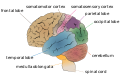

Lateral surface of left cerebral hemisphere, viewed from the side. (Parietal lobe is shown in orange.) | |

الفص الجداري parietal lobe، هو أحد الفصوص الرئيسية الرابعة في قشرة المخ لدى الثدييات. يقع الفص الجداري فوق الفص القذالي وخلف الفص الجبهي والتلم المركزي.